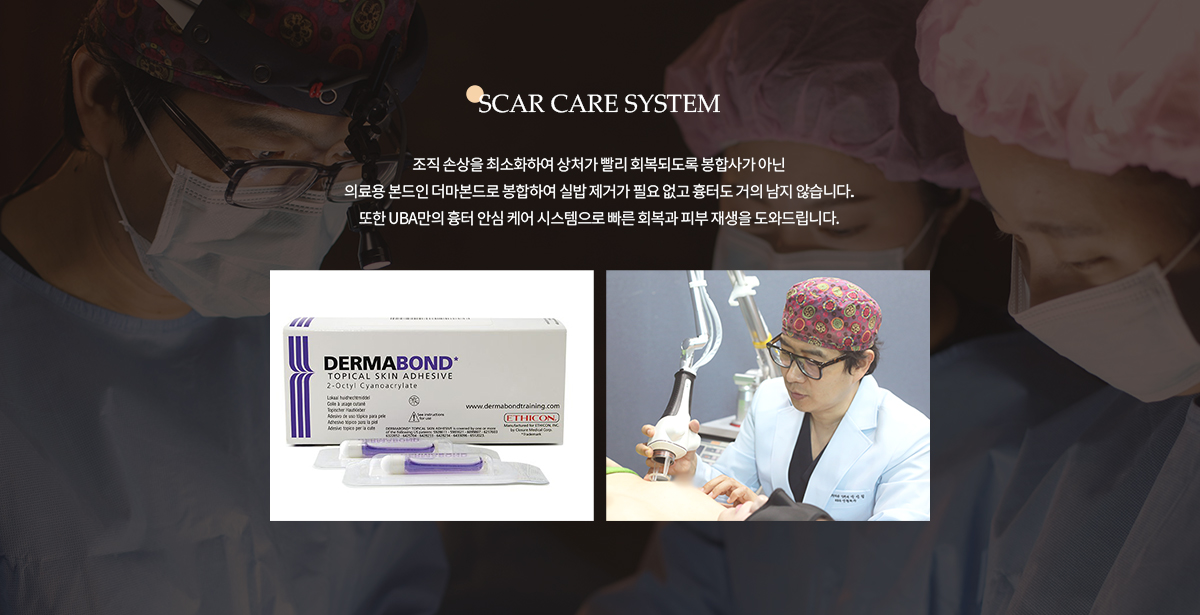

가슴성형 , 흉터를 줄이는 봉합법 더마본드의 모든것!!

가슴성형 , 흉터를 줄이는 봉합법 더마본드의 모든것!!